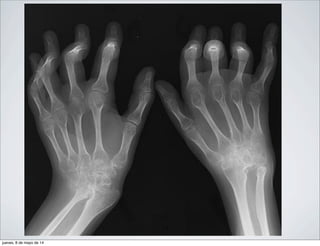

SIGNOS ASOCIADOS:

• ENGROSAMIENTO DE PARTES

BLANDAS

• DESMINERALIZACION EN BANDAS

• PINZAMIENTO DE LA INTERLINEA

ARTICULAR

• MANOS: CARPITIS REUMATOIDE

•CADERA: PINZAMIENTO GLOBAL DE

LA INTERLINEA SEGUIDA DE

PROTRUSION ACETABULAR

Rx AP de ambas manos de un paciente con AR. Se

observa una osteoporosis yuxtaarticular importante

especialmente en las articulaciones

metacarpofalángicas de ambas manos